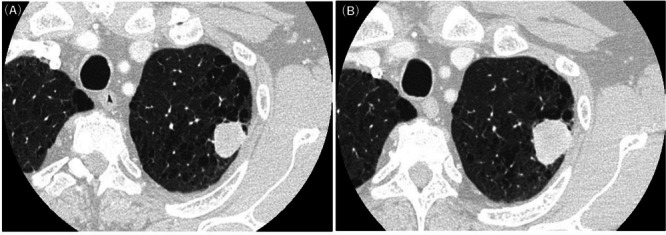

肺癌肉瘤是一种罕见的由非小细胞癌和肉瘤成分组成的肿瘤,大多数病例分化较差。我们报告一例具有分化良好的癌性成分的癌性肉瘤,需要与畸胎瘤衍生的肿瘤进行鉴别诊断,如畸胎瘤癌性肉瘤。我们提出一个68岁的男性病例,他到我们医院检查一个22毫米的肺肿瘤。患者行左侧S1+2节段切除术,术后过程平稳。术后21个月随访未见复发。节段切除术标本显示一个黄白色、边界清楚的肿块。肿瘤包括分化良好的鳞状上皮和腺状上皮,以及未成熟梭形细胞、软骨肉瘤和横纹肌肉瘤的肉瘤成分。病人被诊断为癌肉瘤。本病例包含分化良好的癌成分,有必要将其与畸胎瘤肉瘤区分开来。没有神经成分,没有在畸胎癌肉瘤中观察到的SMARCA4丢失,排除了畸胎癌肉瘤。癌肉瘤的特点是双期组织病理学模式,这使得很难在活检中准确诊断,活检只能捕获肿瘤的一部分。即使术前活检怀疑畸胎瘤衍生的肿瘤,也应考虑癌肉瘤的可能性。

Pulmonary carcinosarcoma is a rare tumor composed of non-small-cell carcinomas and sarcomatous elements, which is poorly differentiated in most cases. We present a case of carcinosarcoma with a well-differentiated carcinomatous component that required a differential diagnosis from tumors derived from teratomas, such as teratocarcinosarcoma. We present a case of a 68-year-old man who visited our hospital for an examination of a 22-mm lung tumor. The patient underwent left S1+2 segmentectomy, and his postoperative course was uneventful. No recurrence was observed in the 21-month postoperative follow-up period. The segmentectomy specimen revealed a yellow-white, well-circumscribed mass. The tumor consisted of well-differentiated squamous and glandular epithelia, and sarcomatous components of immature spindle cells, chondrosarcoma, and rhabdomyosarcoma. The patient was diagnosed with carcinosarcoma. This case included well-differentiated carcinomatous components, and it was necessary to differentiate it from teratocarcinosarcomas. There was no neural component, and without SMARCA4 loss, which is observed in teratocarcinosarcoma, and ruled out teratocarcinosarcoma. Carcinosarcomas are characterized by a biphasic histopathological pattern, making it difficult to accurately diagnose them on biopsy, which only captures a portion of the tumor. The possibility of carcinosarcoma should be considered even when the tumors derived from teratomas are suspected on preoperative biopsy.